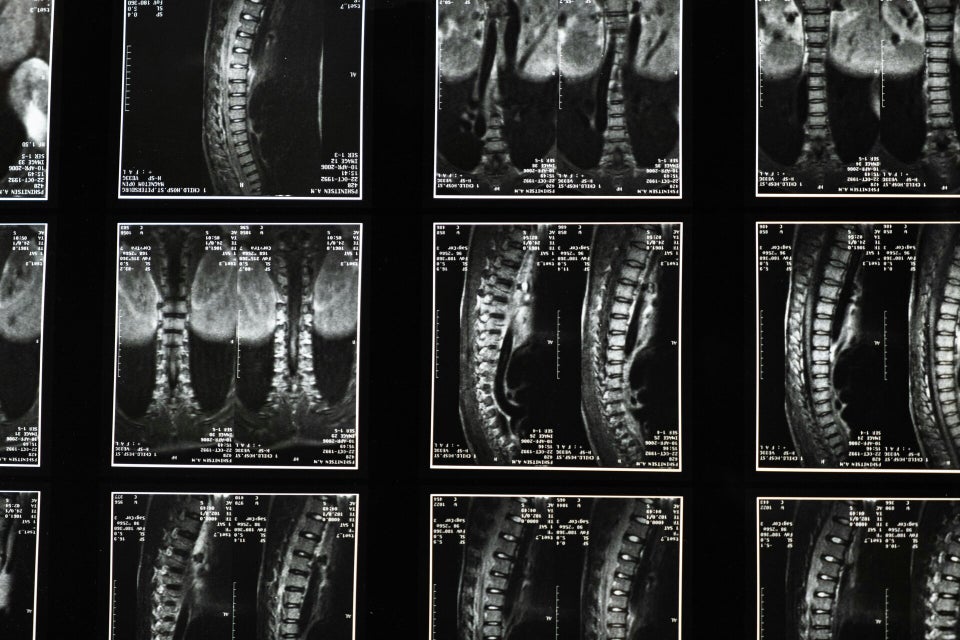

Les lésions médullaires comptent parmi les traumatismes les plus graves qu’une victime puisse subir. Elles surviennent brutalement, bouleversent toute la vie et entraînent souvent des conséquences irréversibles : paraplégie, tétraplégie, ou syndrome de la queue de cheval.

Ces atteintes ne concernent pas uniquement les accidents de la circulation. Elles peuvent aussi résulter d’un accident médical, d’une faute chirurgicale ou encore d’une complication grave / d’un aléa thérapeutique suite à une chirurgie du rachis (arthrodèse, hernie discale, canal lombaire étroit, scoliose, fracture vertébrale).

Certaines chirurgies courantes du rachis peuvent être pourvoyeuses de complications graves : l’arthrodèse, la chirurgie d’hernie discale, l’opération du canal lombaire étroit, la correction d’une scoliose ou encore la prise en charge d’une fracture vertébrale.

Ces interventions, lorsqu’elles se compliquent, peuvent entraîner une paraplégie, une tétraplégie, un syndrome de la queue de cheval ou toute autre atteinte neurologique sévère.